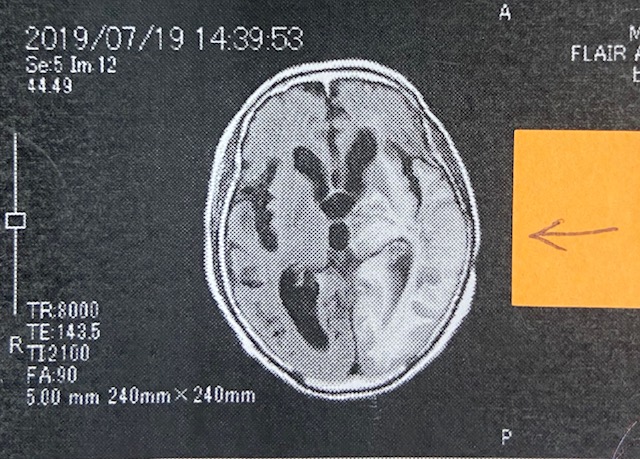

脳腫瘍の浮腫が2カ月で改善された画像です!!

先日、書いてます患者さんの画像をご覧ください。